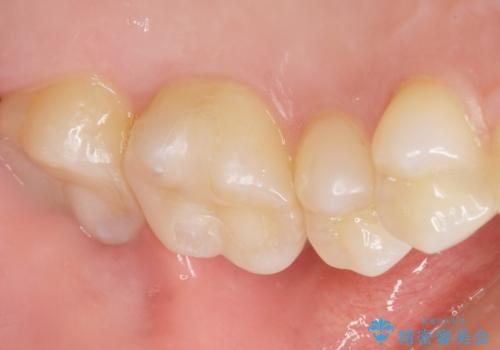

気にされていたフロスをした時のにおいがなくなり、喜んで頂けました。

治療終了後半年のメンテナンス時には「咬み合わせもばっちりです!」とおっしゃって下さいました。

インレーの種類:セラミックインレー e-max press

不適合なレジンを除去し、セラミックインレーによる治療を行いました。(右上76左上67右下7の計5本)